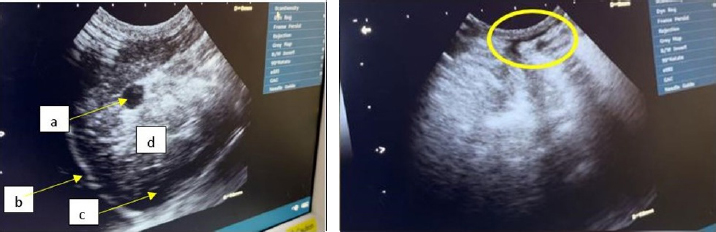

The findings from the ultrasound assessment revealed that the cardiac organ exhibited a normal structure (Fig. 5). The inability of researchers to utilize color flow Doppler imaging, a modality that permits direct visualization of blood flow velocity within the heart and related blood vessels, and consequent description of turbulent blood flow patterns, has precluded observation of blood flow in the heart of the Hiro cat.

Fig. 5. Ultrasound results of cat Hiro’s heart structure, (left: long axis, right: short axis) right parasternal view position.

Ascites represent a clinical symptom manifestation of heart failure (Goh et al., 2022; Damara et al., 2023). The physical examination of the heart organ through auscultation revealed findings of a murmur (sound). Murmurs of the heart can be attributed to the narrowing (stenosis) of heart valves or the imperfect closing (insufficiency) of the heart valves, resulting in rapid blood flow to the heart (Santoso et al., 2021). Based on an unusual listening examination of the heart, a supplementary assessment is conducted to obtain more information about the heart’s condition. The additional tests carried out included a lateral and dorsoventral X-ray examination and an ultrasound examination. Unfortunately, due to the unavailability of certain tools, blood flow in the heart chambers could not be observed.